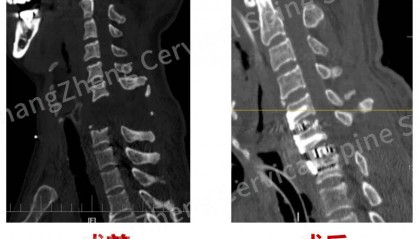

全球罕见!“身首离断”患者被救回 主刀医生:术毕两月整,已脱离呼吸机半月

8月18日,海军军医大学第二附属医院(上海长征医院)对一例“身首离断”式的罕见严重颈椎骨折脱位的患者...

全球罕见!中国医生救回“身首离断”患者

从业近30年,上海长征医院颈椎外科病区主任陈华江教授接诊过无数凶险的颈椎外伤患者,但称得上是“身首离...